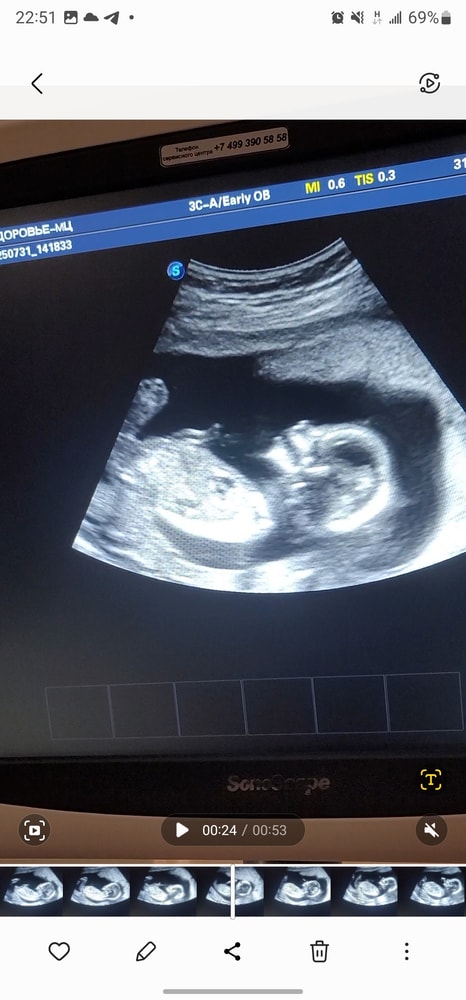

Ждём доченьку 😊🥰 УЗИ 15 недель

Пол малышаВ четверг ходила на узи, где врач дал 80% гарантии на девочку. В предыдущем посте кидала фото с узи)